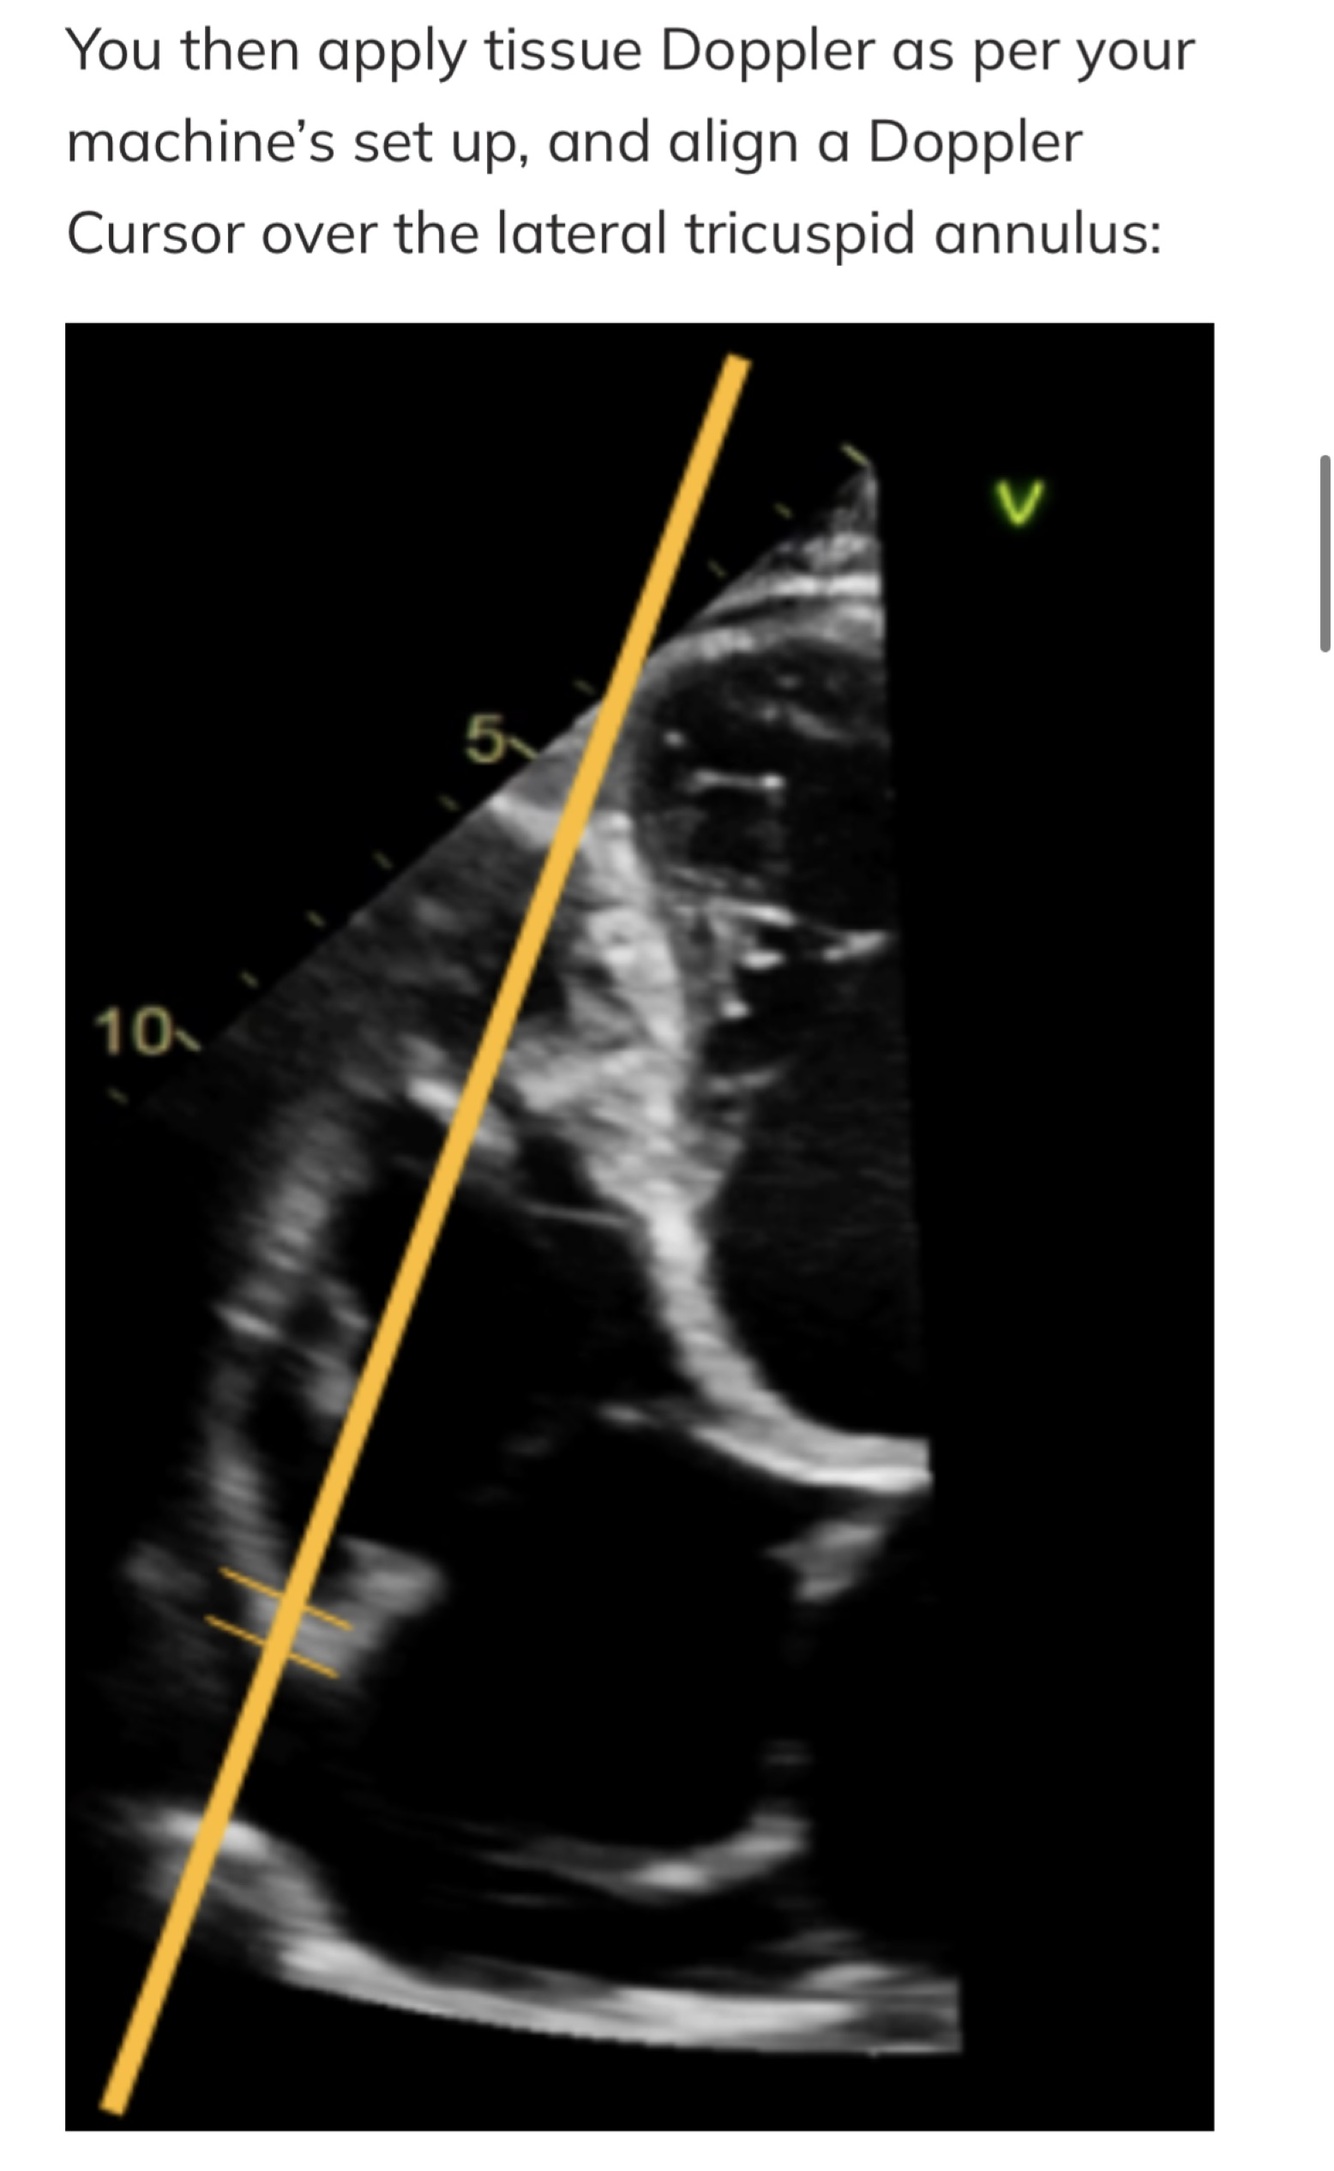

RV function index: s’

Lateral tricuspid annulus peak systolic velocity

Correlates with RV EF and RV dysfunction

Normal: S’ > 10cm/sec

Cons: angle dependent, longitudinal measurement